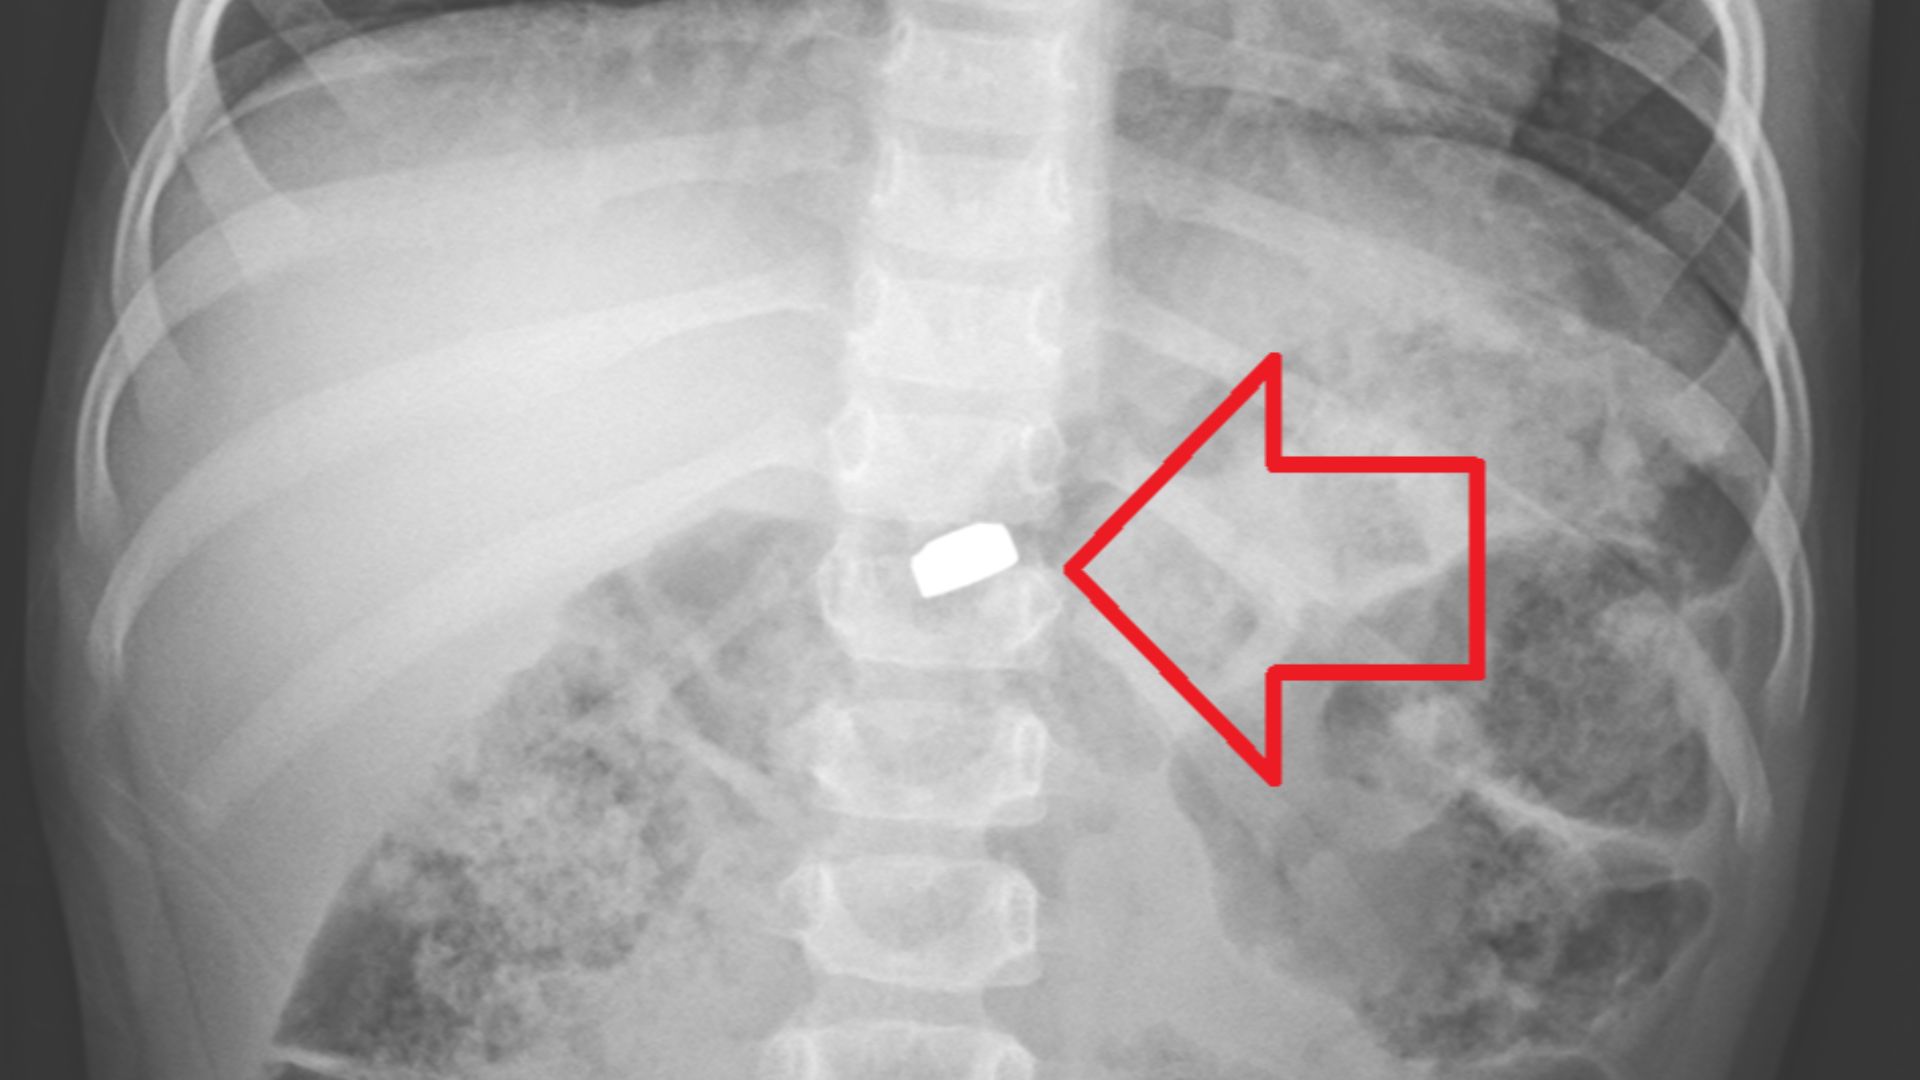

3. Magnets

A single magnet isn’t the end of the world, but two can be catastrophic. When swallowed, they attract through intestinal walls and cause perforations. Kids love that satisfying click sound when magnets connect and are often inspired to see if it tastes as good as it sounds.